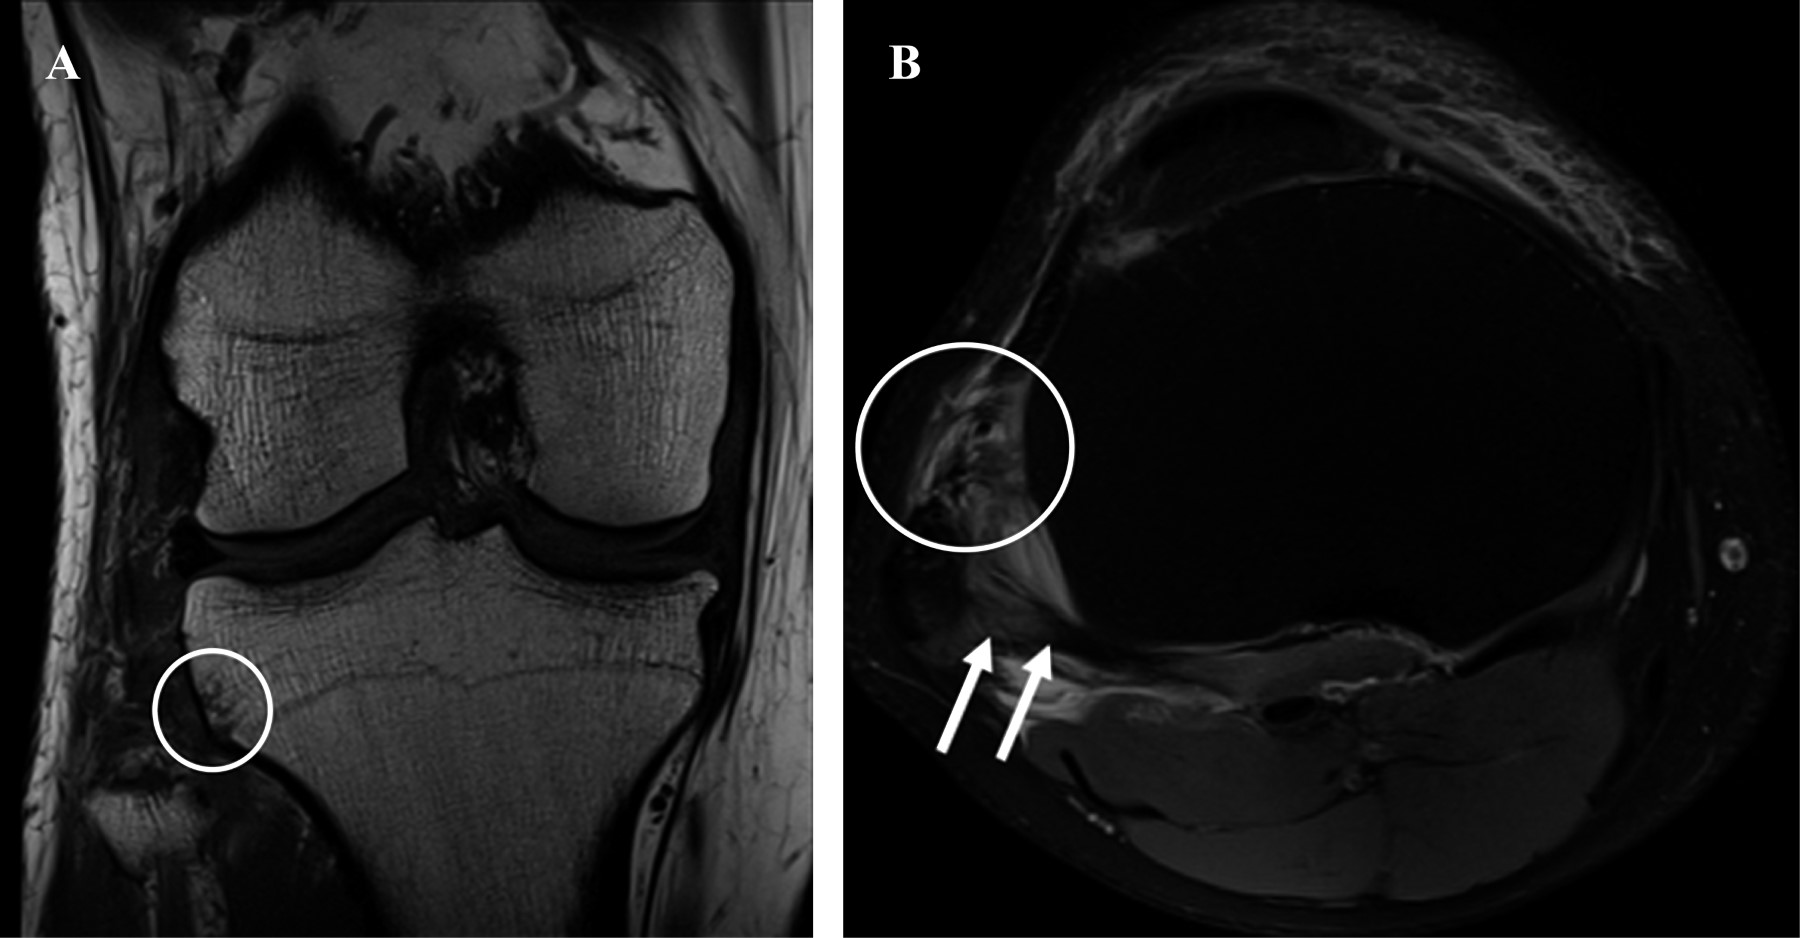

Manteniendo la sospecha de una LTFP se decidió continuar estudio con TC; sin embargo, el paciente rechaza estudio en agudo debido a pandemia por Coronavirus 2019 (COVID-19), cuadro poco sintomático y sin lesiones óseas evidentes. Por lo tanto, se agenda estudio con RM para considerar el diagnóstico diferencial dentro de las próximas 24 horas. Las imágenes de la RM presentan signos sugerentes LTFP anterolateral: contusión ósea marginal en el aspecto anterolateral de la tibia, lesión de los ligamentos tibiofibulares anterosuperior y posterosuperior y un esguince de bajo grado de la esquina posterolateral caracterizado por desgarro parcial del músculo y tendón poplíteo (Figura 2). El paciente es contactado de manera urgente; sin embargo, refiere haber sentido un clank previo a la llamada, con alivio completo de molestias y ausencia del aumento de volumen en zona lateral de rodilla derecha, logrando carga y ROM completo de forma asintomática. Se indica control con nuevas imágenes, lo que debió postergarse debido a situación actual COVID-19. Se sigue al paciente por tres meses a través de consulta online, manteniendo una rodilla asintomática y funcionalidad normal. Por último, se realiza un control clínico con una RM que objetivan una articulación tibiofibular proximal estable y reducida, respectivamente.

La resonancia magnética (RM) también puede asistir como imagen complementaria para la confirmación diagnóstica.8,21 Tiene la ventaja adicional de ser una excelente herramienta para evaluar partes blandas, permitiendo por un lado pesquisar lesiones ligamentarias asociadas a las LTFP y por el otro, ser de utilidad en el diagnóstico diferencial ante dudas diagnósticas.8,19,21 Sin embargo, tampoco se han descrito valores de normalidad para la articulación tibiofibular proximal en RM y tiene la desventaja de ser un recurso con accesibilidad limitada, eleva los costos y puede retrasar el diagnóstico.8